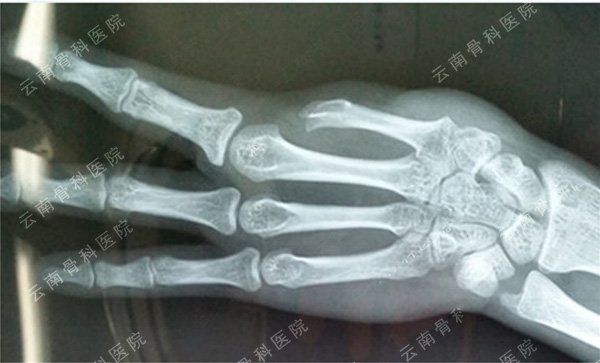

示指长手指再造(1)

示指长手指再造(2)

示指指尖修饰性再造